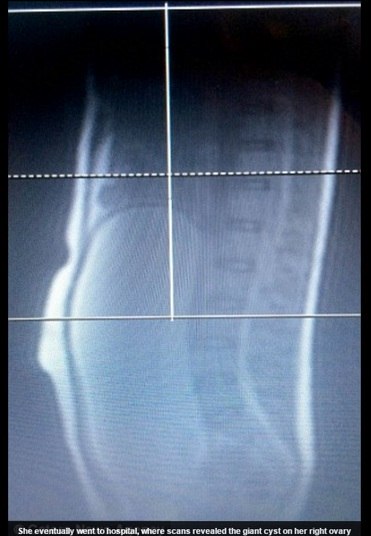

A primeira vez que Olivia percebeu algo de diferente em seu corpo foi

durante as férias de 2013. Mas foi só em novembro de 2014 que ela começou de

fato a sentir dores, e que sua barriga dobrou de tamanho. Exames mostraram o

cisto de 30 cm, e um tumor em seu interior — ambos já tinham “engolido” o

ovário de Olivia, além de sua trompa. Com isso, ambos precisariam ser removidos

em uma cirurgia.